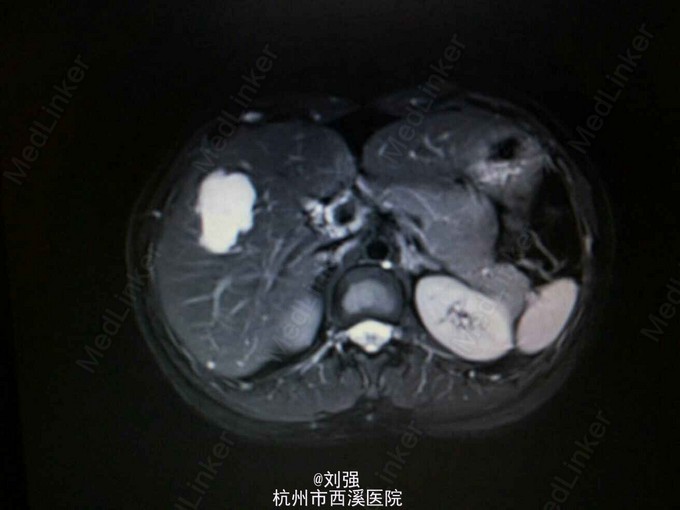

患者40岁女性,因“肝区疼痛2月余,加重10余天”入院。1个月前到外院就诊,腹部CT提示肝S5血管瘤。既往有"胃溃疡"病史。余病史无特殊。

查体:生命体征平稳,心肺无特殊。腹部外形正常,腹式呼吸存在,无压痛以及反跳痛,肝区叩击痛阳性。辅助检查:实验室检查提示白蛋白下35.97g/L。腹部彩超提示:肝S5一大小为4.3cmX3.5cm实质性病灶,考虑血管瘤。腹部MRI检查提示S5段血管瘤。